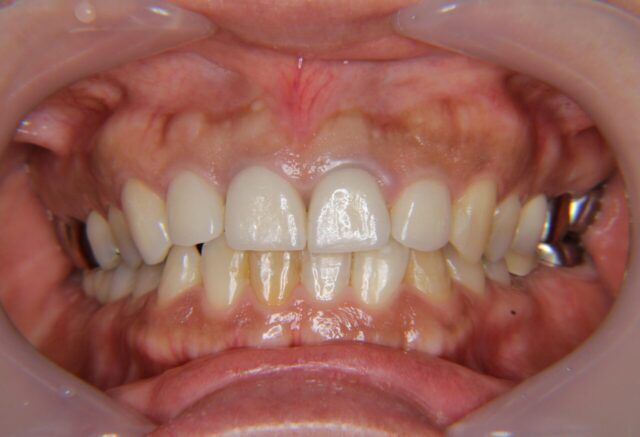

歯周外科処置を含む前歯セラミック治療と臼歯インプラント治療

After

| 主訴 | さし歯が取れた |

| 年齢 | 40代 |

| 性別 | 女性 |

| 治療期間・回数 | 5ヶ月、14回 |

| 治療方法 | 歯周治療、歯周外科手術、セラミック治療、インプラント治療 |

| 費用 | 1,090,800円 |

| デメリット・注意点 | セラミックとインプラントの費用で保険診療分は含まず |

| 備考 | 前歯は5本、e-maxセラミックを使用。 臼歯インプラントは2本、ジルコニアセラミックを使用。 表示されている費用は当時の価格となっています。 前歯を美しく仕上げるため、歯周治療と歯周外科手術を丁寧に行いました。 セラミックは白くて当たり前ですが、歯ぐきとの調和を重視して治療しました。 |